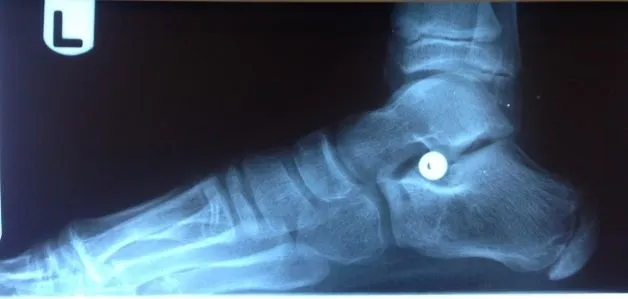

Pre-operative x-rays of the flatfoot with the talus deviated medially due to subluxing off the calcaneus causing the midtarsal joint to sublux laterally and uncovering of the talar head at the talo-navicular joint (left). The talus bone should line up with or be close to paralletl with a line drawn through the 1st metatarsal shaft (right). This is referred to as Meary's angle.

One case see an improvement in Meary's angle after surgical repair of the flatfoot with a subtalar joint implant which blocks the subluxation of the talus off of the calcaneus.